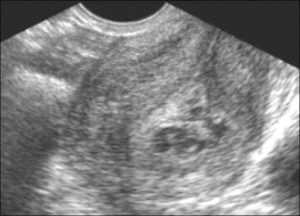

Первое обследование после медикаментозного прерывания беременности необходимо пройти на вторые сутки. Доктор оценит состояние матки, процесс отторжения плодного яйца от стенки. В случае положительной динамики женщину пригласят на контрольное УЗИ через 2 недели.

- Эндометрия (его толщину: слой более 26 мм требует оперативного вмешательства; наличие образований, в том числе остатки плодного яйца: на УЗИ – темное круглое образование в толще слоя).

Проводится визуальный осмотр шейки матки и пальпация. Внутренний зев ее будет расширен, плодный остаток в наличии. УЗИ определит его объем и локализацию, а также общее состояние репродуктивных органов. Биохимический анализ крови расскажет о функционировании органов и систем пациентки.